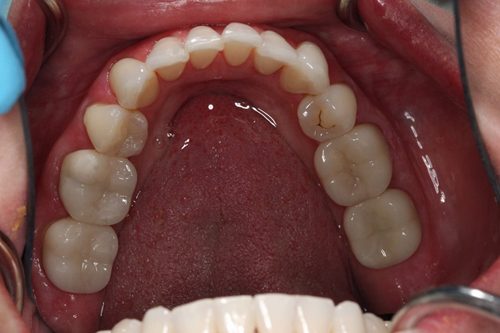

After